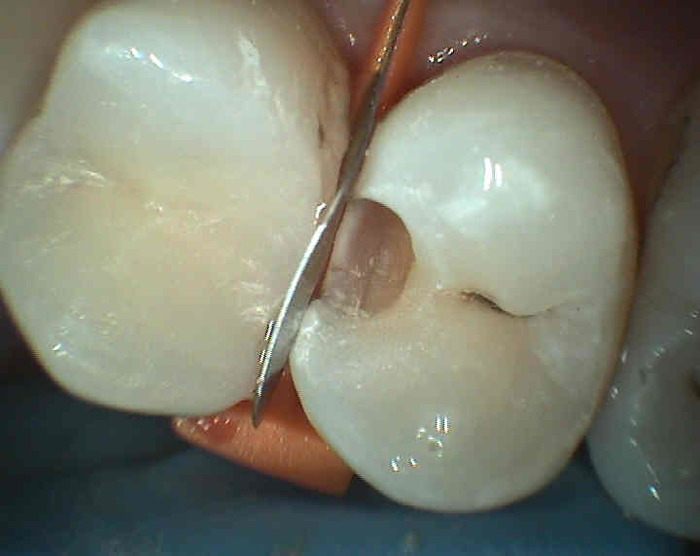

Mechanismus vzniku zubního kazu je následující: Sacharolytické bakterie (zvl.kariogenní streptokoky) rozkládají zkvasitelné zbytky potravy (jednoduché cukry) na organické kyseliny (např. mléčná) a ty rozleptávají (demineralizují, odvápňují) povrch zubní skloviny. Po průniku pod tvrdou a více mineralizovanou sklovinu do méně mineralizované zuboviny (dentinu) obsahující velké množství organických látek, mohou mikrobi přímo "konzumovat" a rozkládat tyto organické látky. V zubovině je z tohoto důvodu šíření zubního kazu rychlejší. Dosáhne -li kaz blízkosti zubní dřeně ("zubní nerv") dojde k zánětu zubní dřeně a posléze k odumření zubu. Neošetřený mrtvý zub se může později projevit zánětem ozubice.

Příznaky zubního kazu : zdrsnění povrchu zubu, ulpívání zbytků potravy, bolestivost na podráždění (chlad, sladké, někdy při skusu), v mezizubním prostoru se může trhat zubní nit ( ostré okraje kazivé dutiny).